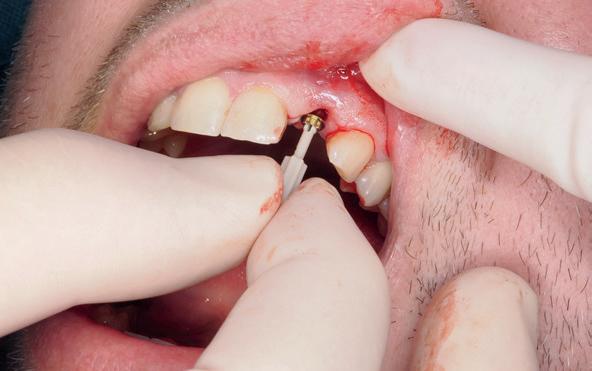

Implantologische behandelingen in het esthetische front vragen meer dan technische vaardigheid alleen. Ze vragen om overzicht, timing, vertrouwen en een team dat als vanzelf samenwerkt onder druk. Juist bij complexe casussen, waarin angst, infectie en hoge esthetische verwachtingen samenkomen, wordt zichtbaar hoe bepalend de rol van de tandartsassistent is.

Deze casus beschrijft een uitgebreide immediate implantaatbehandeling bij een patiënt die door meerdere collega’s werd geweigerd. Niet omdat de mogelijkheden ontbraken, maar omdat de complexiteit vroeg om een perfect afgestemde samenwerking. Het verhaal laat zien hoe de assistent in zo’n traject veel meer is dan een uitvoerende kracht of “mal”, maar een dynamische surgical guide die het proces mede stuurt, bewaakt en mogelijk maakt.De patiënt: wanneer alles samenkomt

Ze kwam binnen op een dinsdagochtend, iets voor achten. Een vrouw van begin zeventig, met een zachte stem en ogen die meer vertelden dan haar woorden. Ze vertelde dat ze een eigen B&B had en dat ze zich nauwelijks kon voorstellen gasten te ontvangen zonder tanden. Op dit moment kon ze echter nauwelijks lachen. “Het doet pijn… en het ruikt soms ook niet goed,” zei ze bijna verontschuldigend. Haar oude bovenbrug, die ze al meer dan twintig jaar droeg, was langzaam maar zeker ingestort. Er was sprake van cariës onder meerdere pijlers, pusafvloed,

chronische ontsteking en een brug die mobiel was en elke beet pijnlijk maakte. Ze had inmiddels meerdere tandartsen bezocht. Drie hadden haar geweigerd. Te complex. Te veel wensen. Te onvoorspelbaar.

De kern van haar vraag was eenvoudig en tegelijkertijd uitdagend: Is het mogelijk om mijn huidige brug te dupliceren en een nieuwe brug te vervaardigen met minder complicaties?

De basis van een complexe beslissing

Mijn behandelplan begint altijd met een uitgebreid klinisch onderzoek. Dat omvat een medische anamnese, intra- en extra-orale camerafoto’s en uitgebreid verwachtingsmanagement. In deze fase is mijn assistent vooral bezig met het zorgvuldig vastleggen van alle gegevens. Juist dat nauwkeurig documenteren zorgt voor rust in de behandelkamer. Minstens zo belangrijk is het luisteren naar de patiënt. Niet alleen naar de klachten, maar naar het

levensverhaal en de mens achter de brug. Begrijpen wat deze behandeling voor iemand betekent, is cruciaal voor het uiteindelijke succes.

Na het klinische onderzoek volgde het röntgenologisch traject. De CBCT liet precies zien wat we al vreesden: een front waarin het bot onregelmatig was, duidelijke radiolucenties rond de pijlers en een infectiegebied dat zich onder vrijwel de gehele brug had verspreid. Tegelijkertijd was er ook potentie. Net voldoende botstructuur om immediate implantaatplaatsing te overwegen, mits alles perfect gepland zou worden.